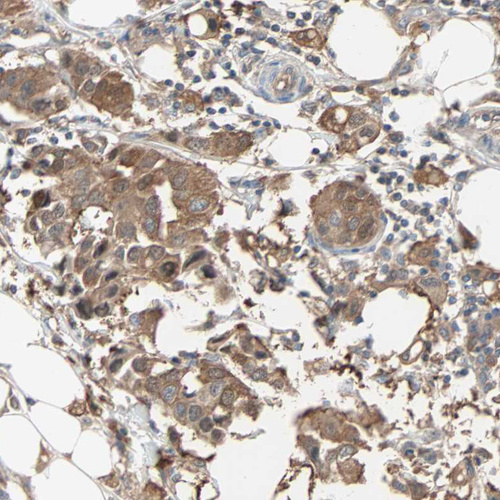

Immunohistochemical staining of human breast cancer shows strong cytoplasmic positivity in tumor cells.